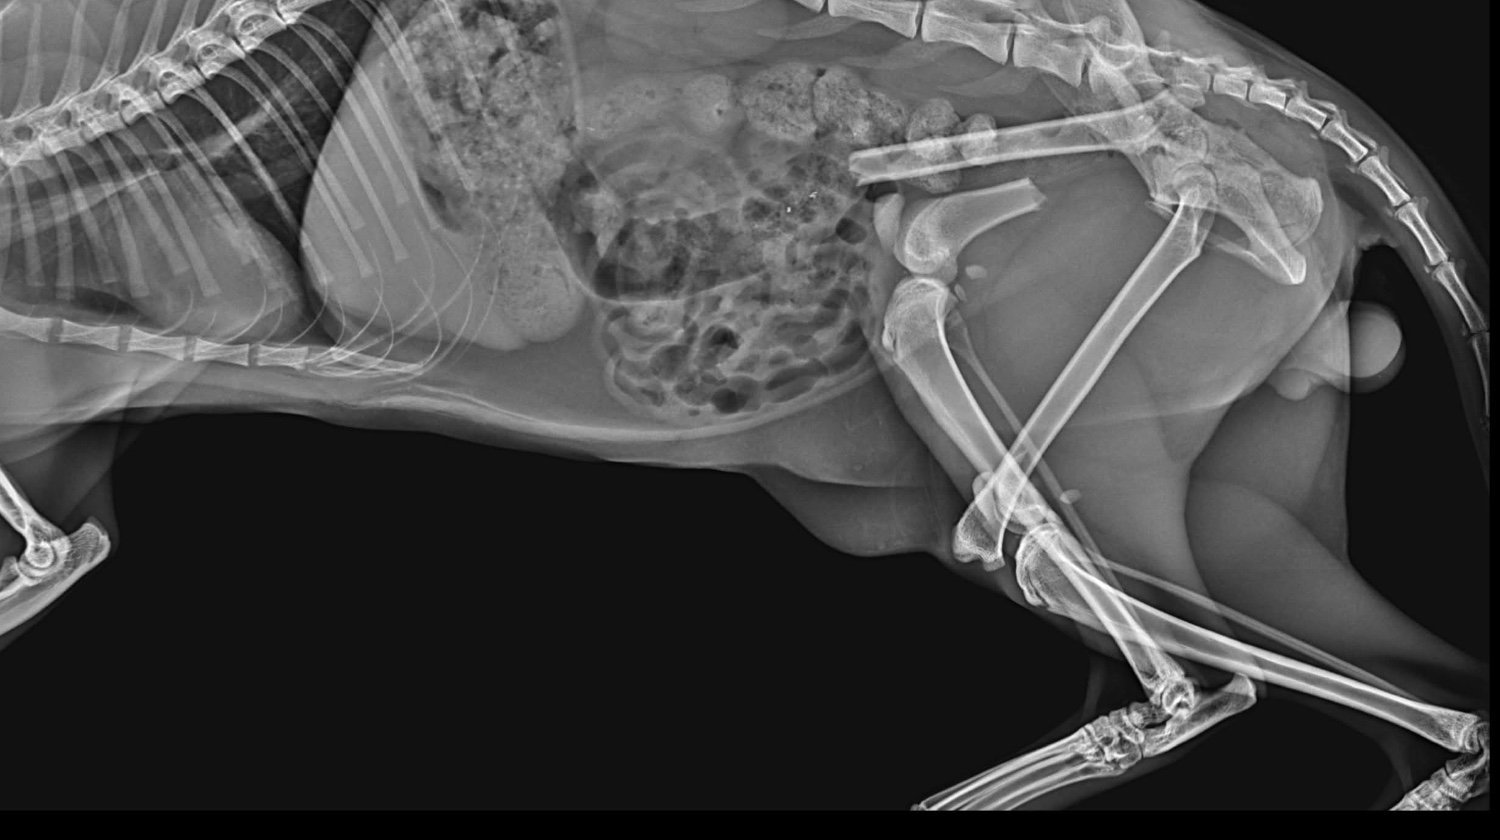

Lucky je maček, ki so ga pred nekaj dnevi našli pred blokom, v katerem živi moj brat. Luckyja je takoj odpeljal k veterinarju. Po posvetu je ugotovil, da ima poškodovani obe nogi in medenico :(. Natančneje, ima naslednje težave:

Medenica

obojestranska sakroiliakalna dismoreksija

Zlom desne iliakalke s premikom

Zadnje okončine

Diafizni zlom v srednji tretjini, poševni, s premikom, brez kostne eklatantnosti, na ravni stegnenice femurulolistangii

Zlom tipa SH I distalno od desne stegnenice

Slikovna diagnoza: zlom leve stegnenice, SH zlom desne stegnenice, obojestranski križno-iliakalni izpah, zlom desne iliakalne palete

Po opravljenih rentgenskih posnetkih, kjer so bile ugotovljene

zgoraj, so ga odpeljali k ortopedu in bo potreboval 3 operacije: po eno za vsako nogo + operacijo medenice.